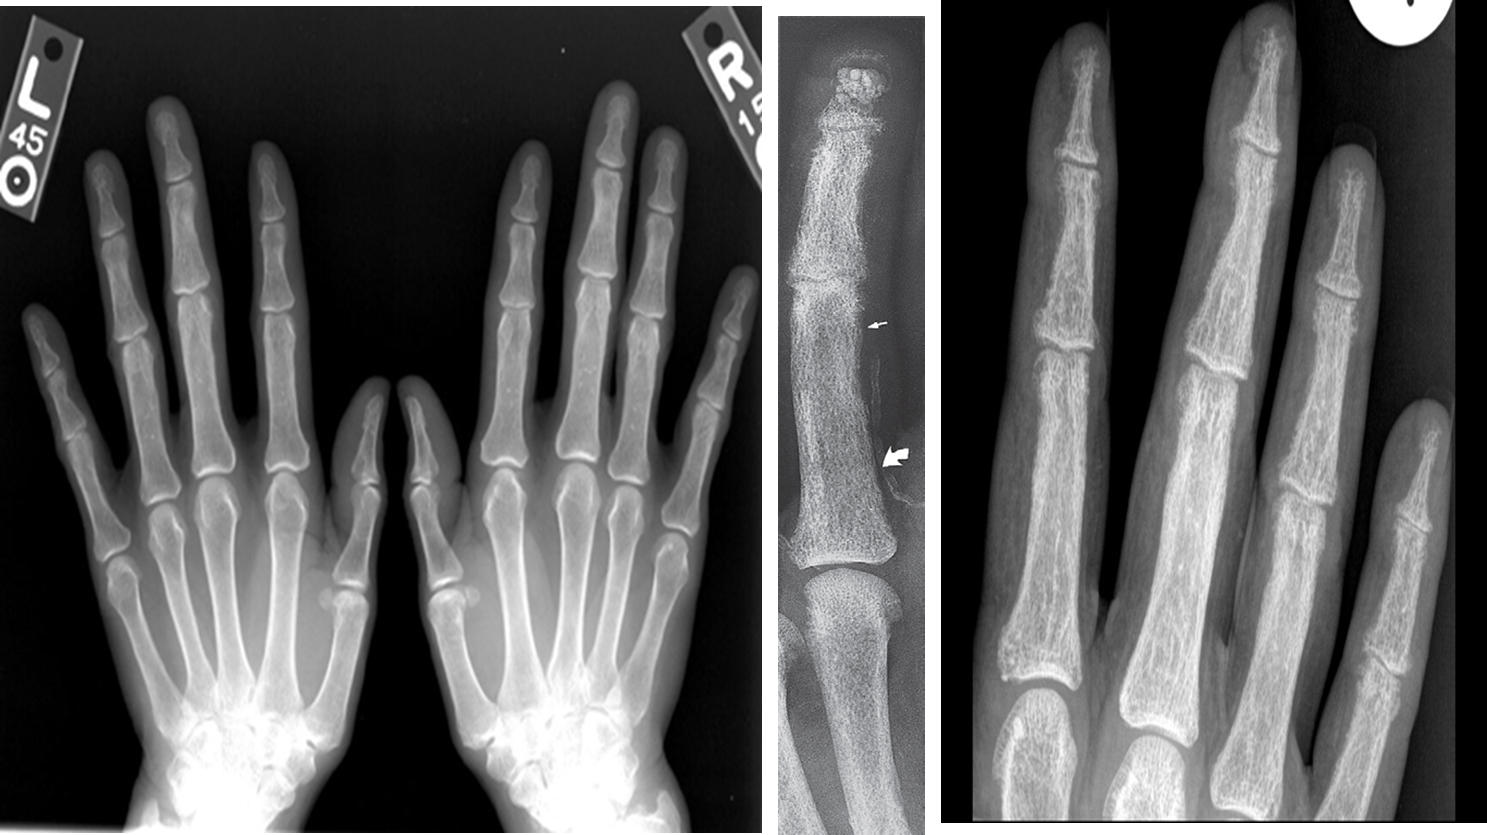

- In hand, sub-periosteal bone resorption .This change usually happen in the middle phalanges, radial aspect in the 2nd or 3rd finger.

- Terminal tuft erosion.

Sub-periosteal bone resorption

- Most useful sign

- Virtually Diagnostic

Subperiosteal bone resorption (straight arrow), resorption of the tip of the terminal phalanx and the altered bone architecture. Arterial calcification is also present (curved arrow).